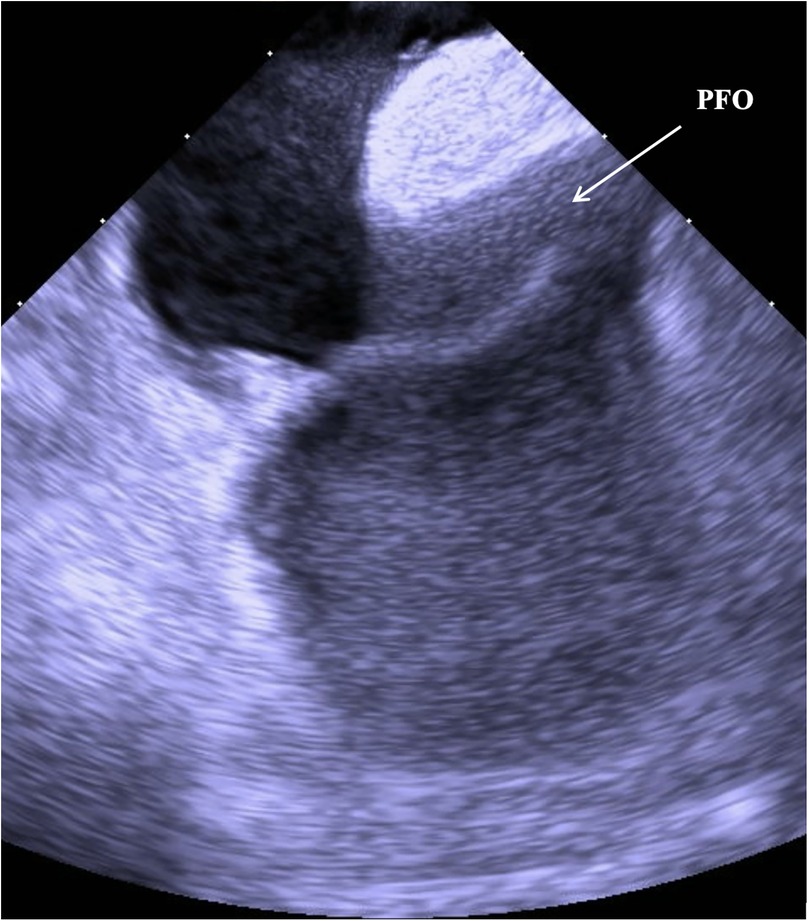

An 80-year-old man presented with progressive dyspnea and severe hypoxemia refractory to high-flow oxygen therapy, ultimately found to have a large persistent patent foramen ovale (PFO) mediated right-to-left-shunt (RTLS). The patient underwent successful percutaneous PFO closure via a 35 mm Amplatz septal occluder guided by intracardiac echocardiography (ICE), resulting in complete resolution of the patient's hypoxia within 24 hours. This case highlights the workup of systemic refractory hypoxemia, the importance of cardiac shunt physiology in considering a RTLS, and the utility of PFO closure under ICE-guidance. For patients with a PFO-mediated RTLS, percutaneous closure offers an effective therapeutic option.